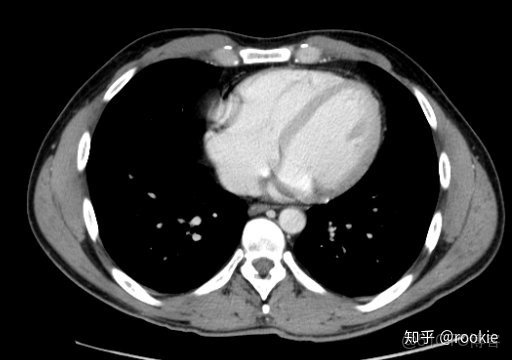

CTA窗口窗口設置: (W:600,L:170)或(W:650,L:225)優點: 在評估CT血管造影研究(或在血管中具有明顯對比的CT掃描的任何階段)時,此設置可用於嘗試清晰地觀察血管病變。它在提供目標血管信號的同時具有良好的平衡,而無需血管內的亮度過高會沖洗腔內病變。

CLAHE算法增強局部對比度的X光圖像增強效果對比_ico_14

此窗口用於在感興趣的血管中有相當大的對比度的情況下(例如CT血管造影)。